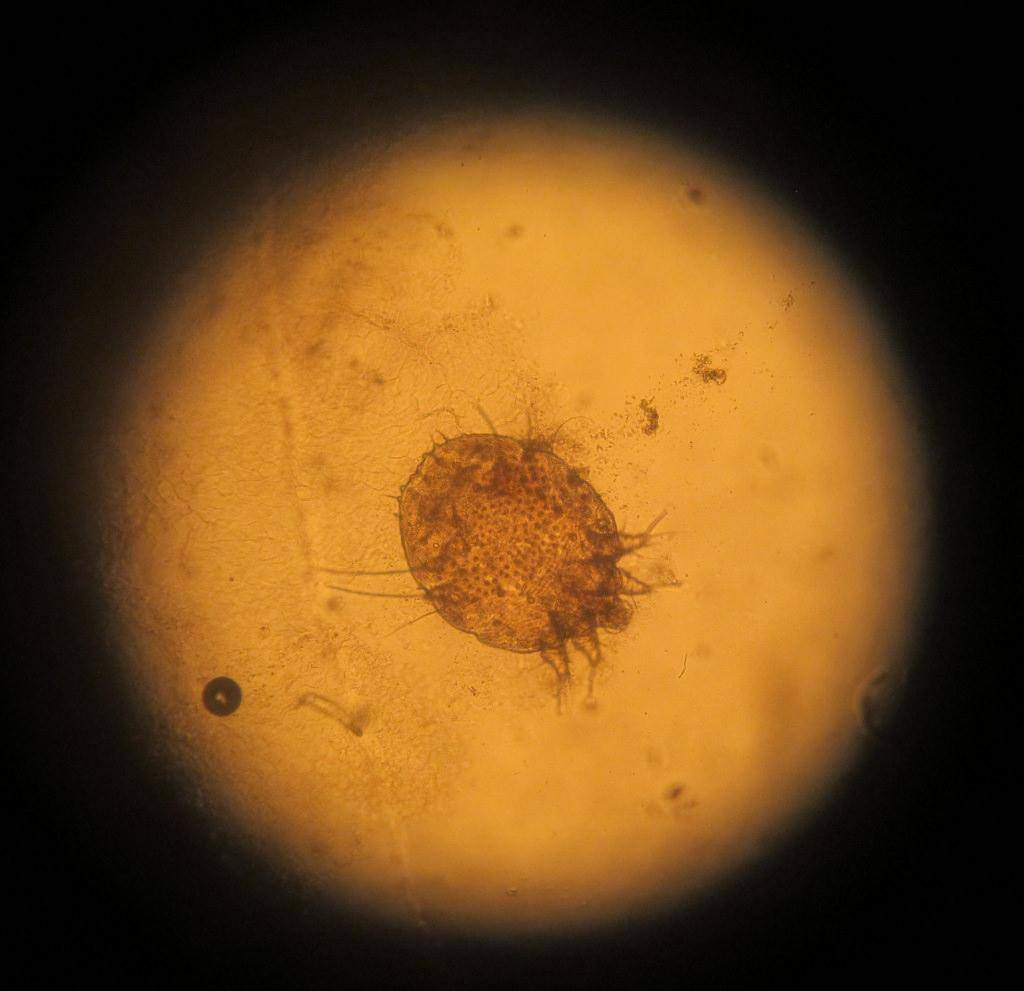

Причина появления поражений – паразит Sarcoptes scabiei. Переносить его может любое живое существо, которое подверглось заражению. И чем больше поражений на теле больного, тем выше риск, что он может кого-то заразить.

как выглядит чесоточный клещ

Заражение осуществляют самки и личинки. Самка обитает в коже. В дневное время она неактивна, но вечером она активно прогрызает ходы, размножается, питается и выделяет продукты переработки. Следовательно, самый большой риск заразиться появляется именно в вечернее-ночное время, когда клещ проявляет большую активность.

Болезнь быстро распространяется по причине того, что самка откладывает яйца, из которых вылупляются личинки. После созревания последние выползают наружу для спаривания. Самец погибает, а самка снова внедряется в кожу человека, чтобы продолжить цикл размножения и распространения.

Паразитарное заболевание, вызванное клещами (насекомыми маленького размера).

Без специальных лабораторных анализов данные паразиты не обнаруживаются.

Основные симптомы: сильный нестерпимый зуд (пес может «раздирать себя», что приводит к вторичным инфицированиям).